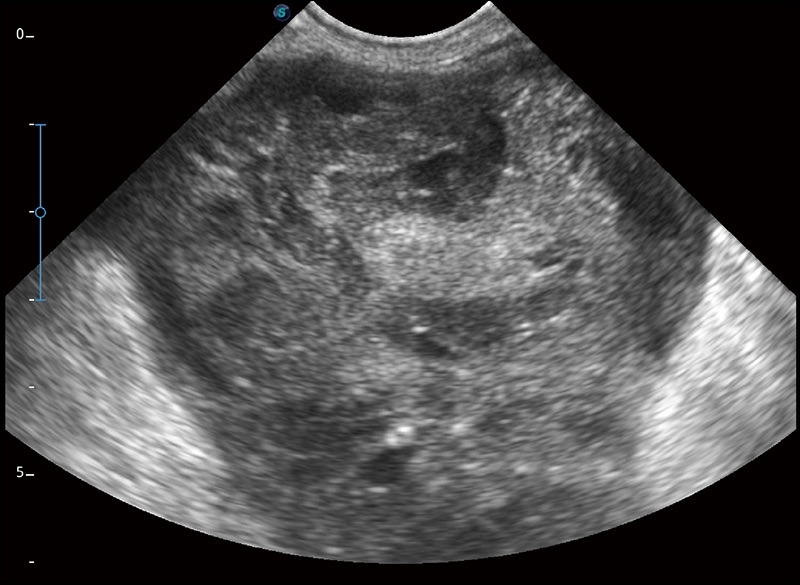

任意波束合成技术

在不牺牲时间分辨率的情况下提供出色的图像

空间复合成像

优化不同角度的图像